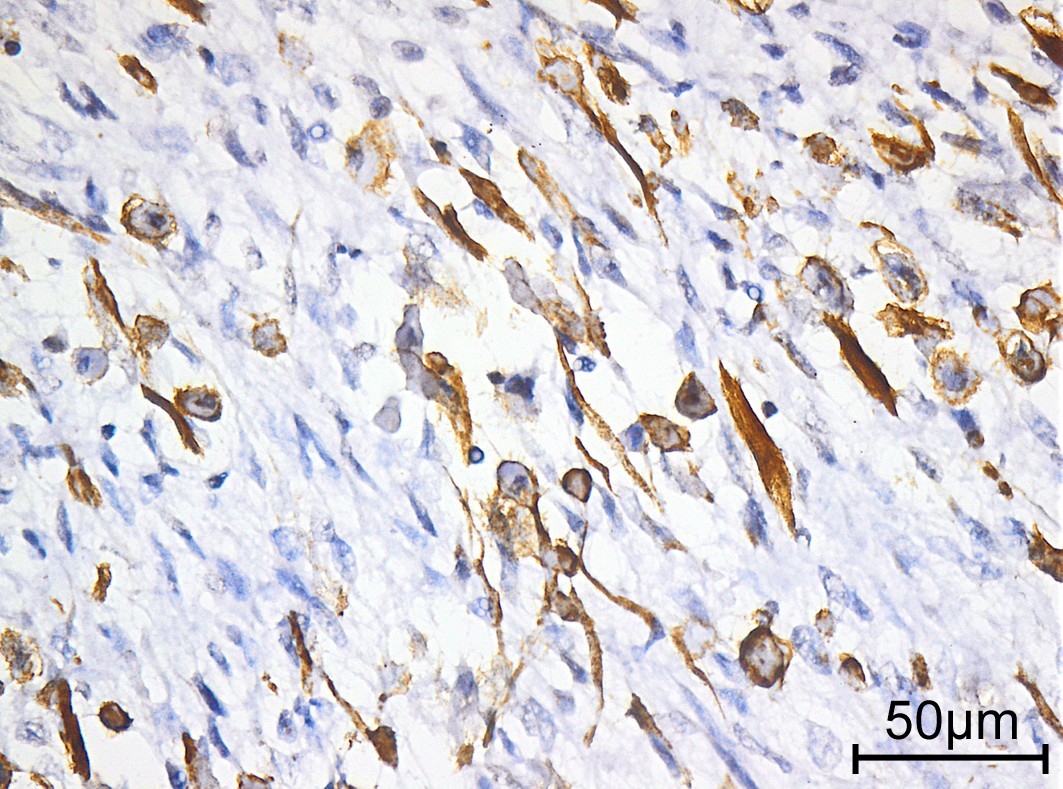

Webpathology.com: A Collection Of Surgical Pathology Images

www.webpathology.com

www.webpathology.com

rhabdomyosarcoma alveolar webpathology pathology comments microscopic

Rhabdomyosarcoma mri tissue sarcomas. Mesothelial cells ascites,mesothelial cells in ascitic fluid,reactive. Rhabdomyosarcoma alveolar webpathology pathology comments microscopic